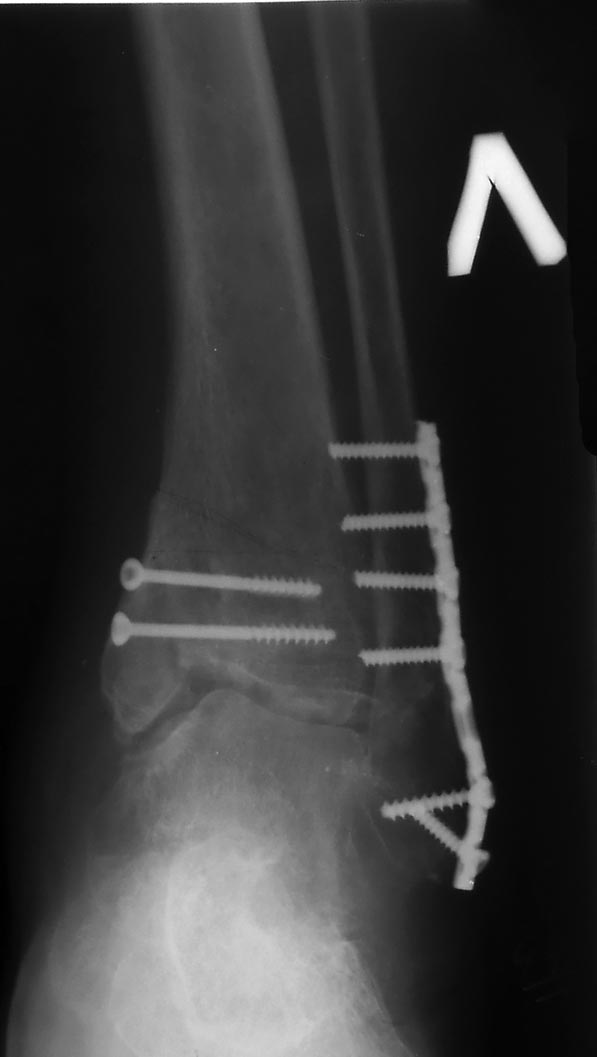

Мужчина, 42 лет, рабочей специальности, соматически здоров. В октябре

2013 года травма на охоте - оступился и подвернул стопу на пахоте -

вывих стопы кнаружи, перелом малоберцовой в нижней трети, внутренней

лодыжки. От предложенного наложения скелетного вытяжения категорически

отказался.

Через 10 дней после поступления в стационар выполнена открытая

репозиция, остеосинтез малоберцовой кости, фиксация внутренней лодыжки

винтами. В настойщий момент патологическая установка стопы, осевая

нагрузка болезненная, амплитуда движений в суставе ограничена. На

приложенных рентгенограммах результат лечения по состоянию на

середину апреля 2014 года. Порекомендовал больному выполнить КТ

голеностопного сустава.